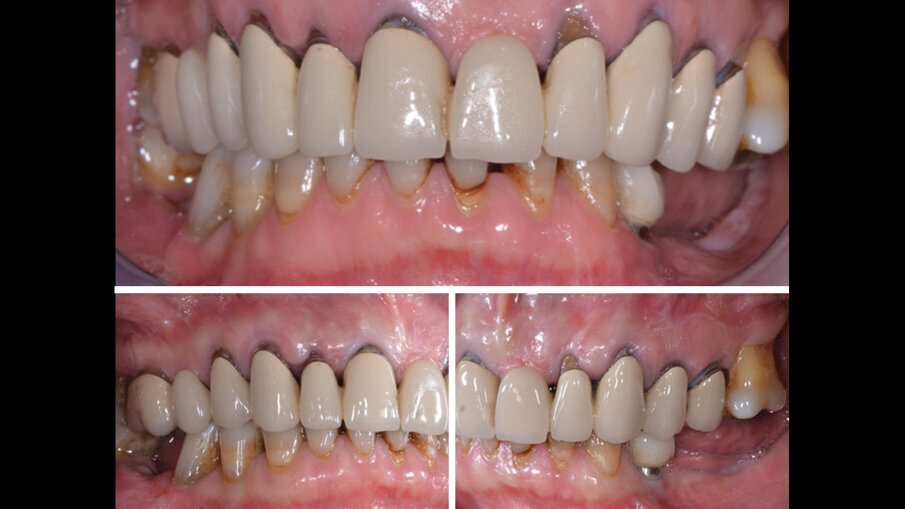

Si presenta alla nostra attenzione un paziente di 60 anni, in apparente buona salute sistemica, che ci trasferisce il desiderio di ringiovanire il suo sorriso (Fig. 1). Non affetta da patologie sistemiche pregresse o in atto, la paziente fuma più di 10 sigarette al giorno e non assume farmaci. Dopo un’attenta visita clinica, vengono prese le impronte e le registrazioni funzionali con l’arco facciale, nonché vengono scattate foto intra ed extra orali, e Opt per permettere lo studio approfondito del caso (Figg. 2, 3). Il caso viene quindi discusso insieme a tutto il team per inquadrare il miglior percorso terapeutico da proporre successivamente alla paziente in un approccio di perfetta concordance.

La riabilitazione protesica inizia con la rimozione del vecchio circolare superiore e nella ripreparazione dei monconi con sostituzione delle porzioni demineralizzate, consecutiva alla ribasatura e rifinitura dei provvisori pre limatura (Fig. 4).Per risolvere il problema estetico di mancanza di gengiva aderente attorno all’elemento 22, effettuiamo un lembo bilaminare con innesto di tessuto connettivo. Utilizzando per lo scollamento a tutto spessore nella parte centrale della recessione un inserto piezo surgery mectron apposito, solleviamo delicatamente il nostro lembo e continuiamo lo scollamento a mezzo spessore intorno al letto di innesto con bisturi (Fig. 5). Successivamente posizioniamo l’innesto di connettivo prelevato dal palato, privato della porzione epiteliale, e suturiamo con punti di sutura staccati in 7.0 sul letto ricevente (Fig. 6).

Fig. 4 - Primo provvisorio superiore.